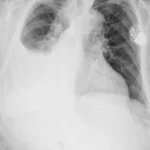

La intoxicación por bloqueadores beta-adrenérgicos es un fenómeno clínico complejo que se asocia a la administración excesiva o inadecuada de fármacos que actúan sobre los receptores beta-adrenérgicos del sistema nervioso…